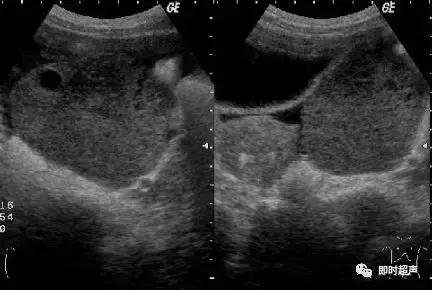

粘液性囊腺瘤(mucinous cystadenoma):占卵巢所有肿瘤20%,恶变率5%,绝大多数单侧,瘤体较大,破裂可造成肿瘤的广泛种植。图象特点:以膈为主,从少量膈到极多量膈,呈多房性,囊壁及膈光滑,液体浑浊,后壁增强效应。10%可见乳头称粘液性乳头状囊腺瘤。

浆液性囊腺瘤(serous cystadenoma):为最常见的卵巢肿瘤,占卵巢肿瘤的27%。大部分为良性,但有较高的恶性变倾向,约有45%-50%可变为恶性。常为单侧性。图象特点:多为单房、壁薄、光滑、边界清,内部回声少,内有光带分隔为多房性,后壁回声增强。囊肿内壁显示有乳头状实质光团则为乳头状浆液性囊腺瘤。